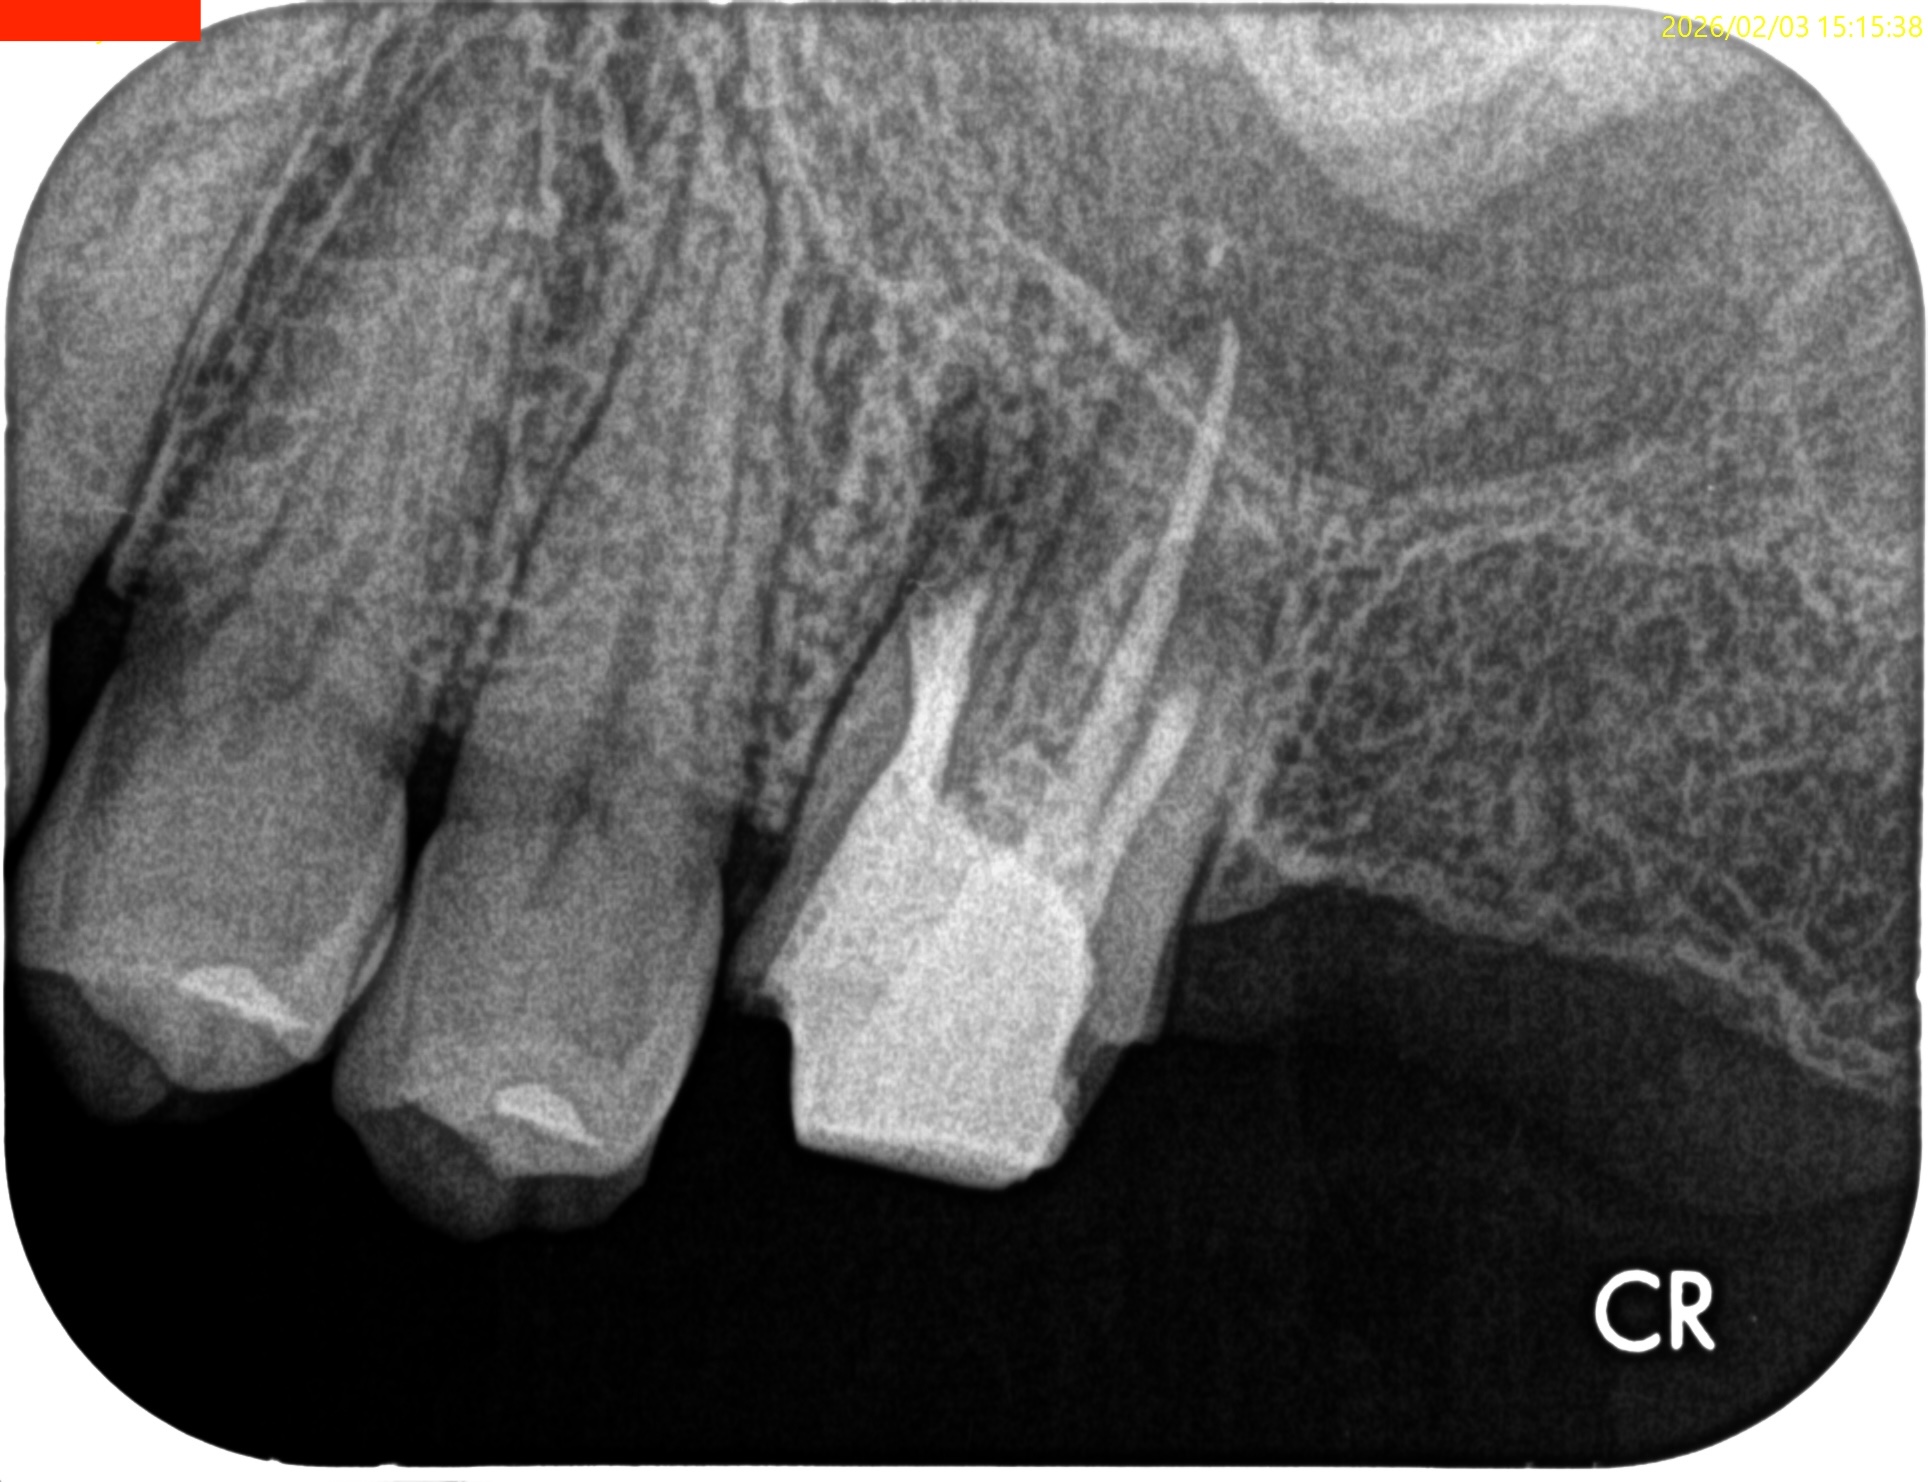

#14 RCT 2yr recall(2026.1.21)

MB,DBの根尖部に病変が残存している。

臨床検査での咬合痛が生活に支障があるそうだ。

#14 MB,DB Apicoectomyが必要である。